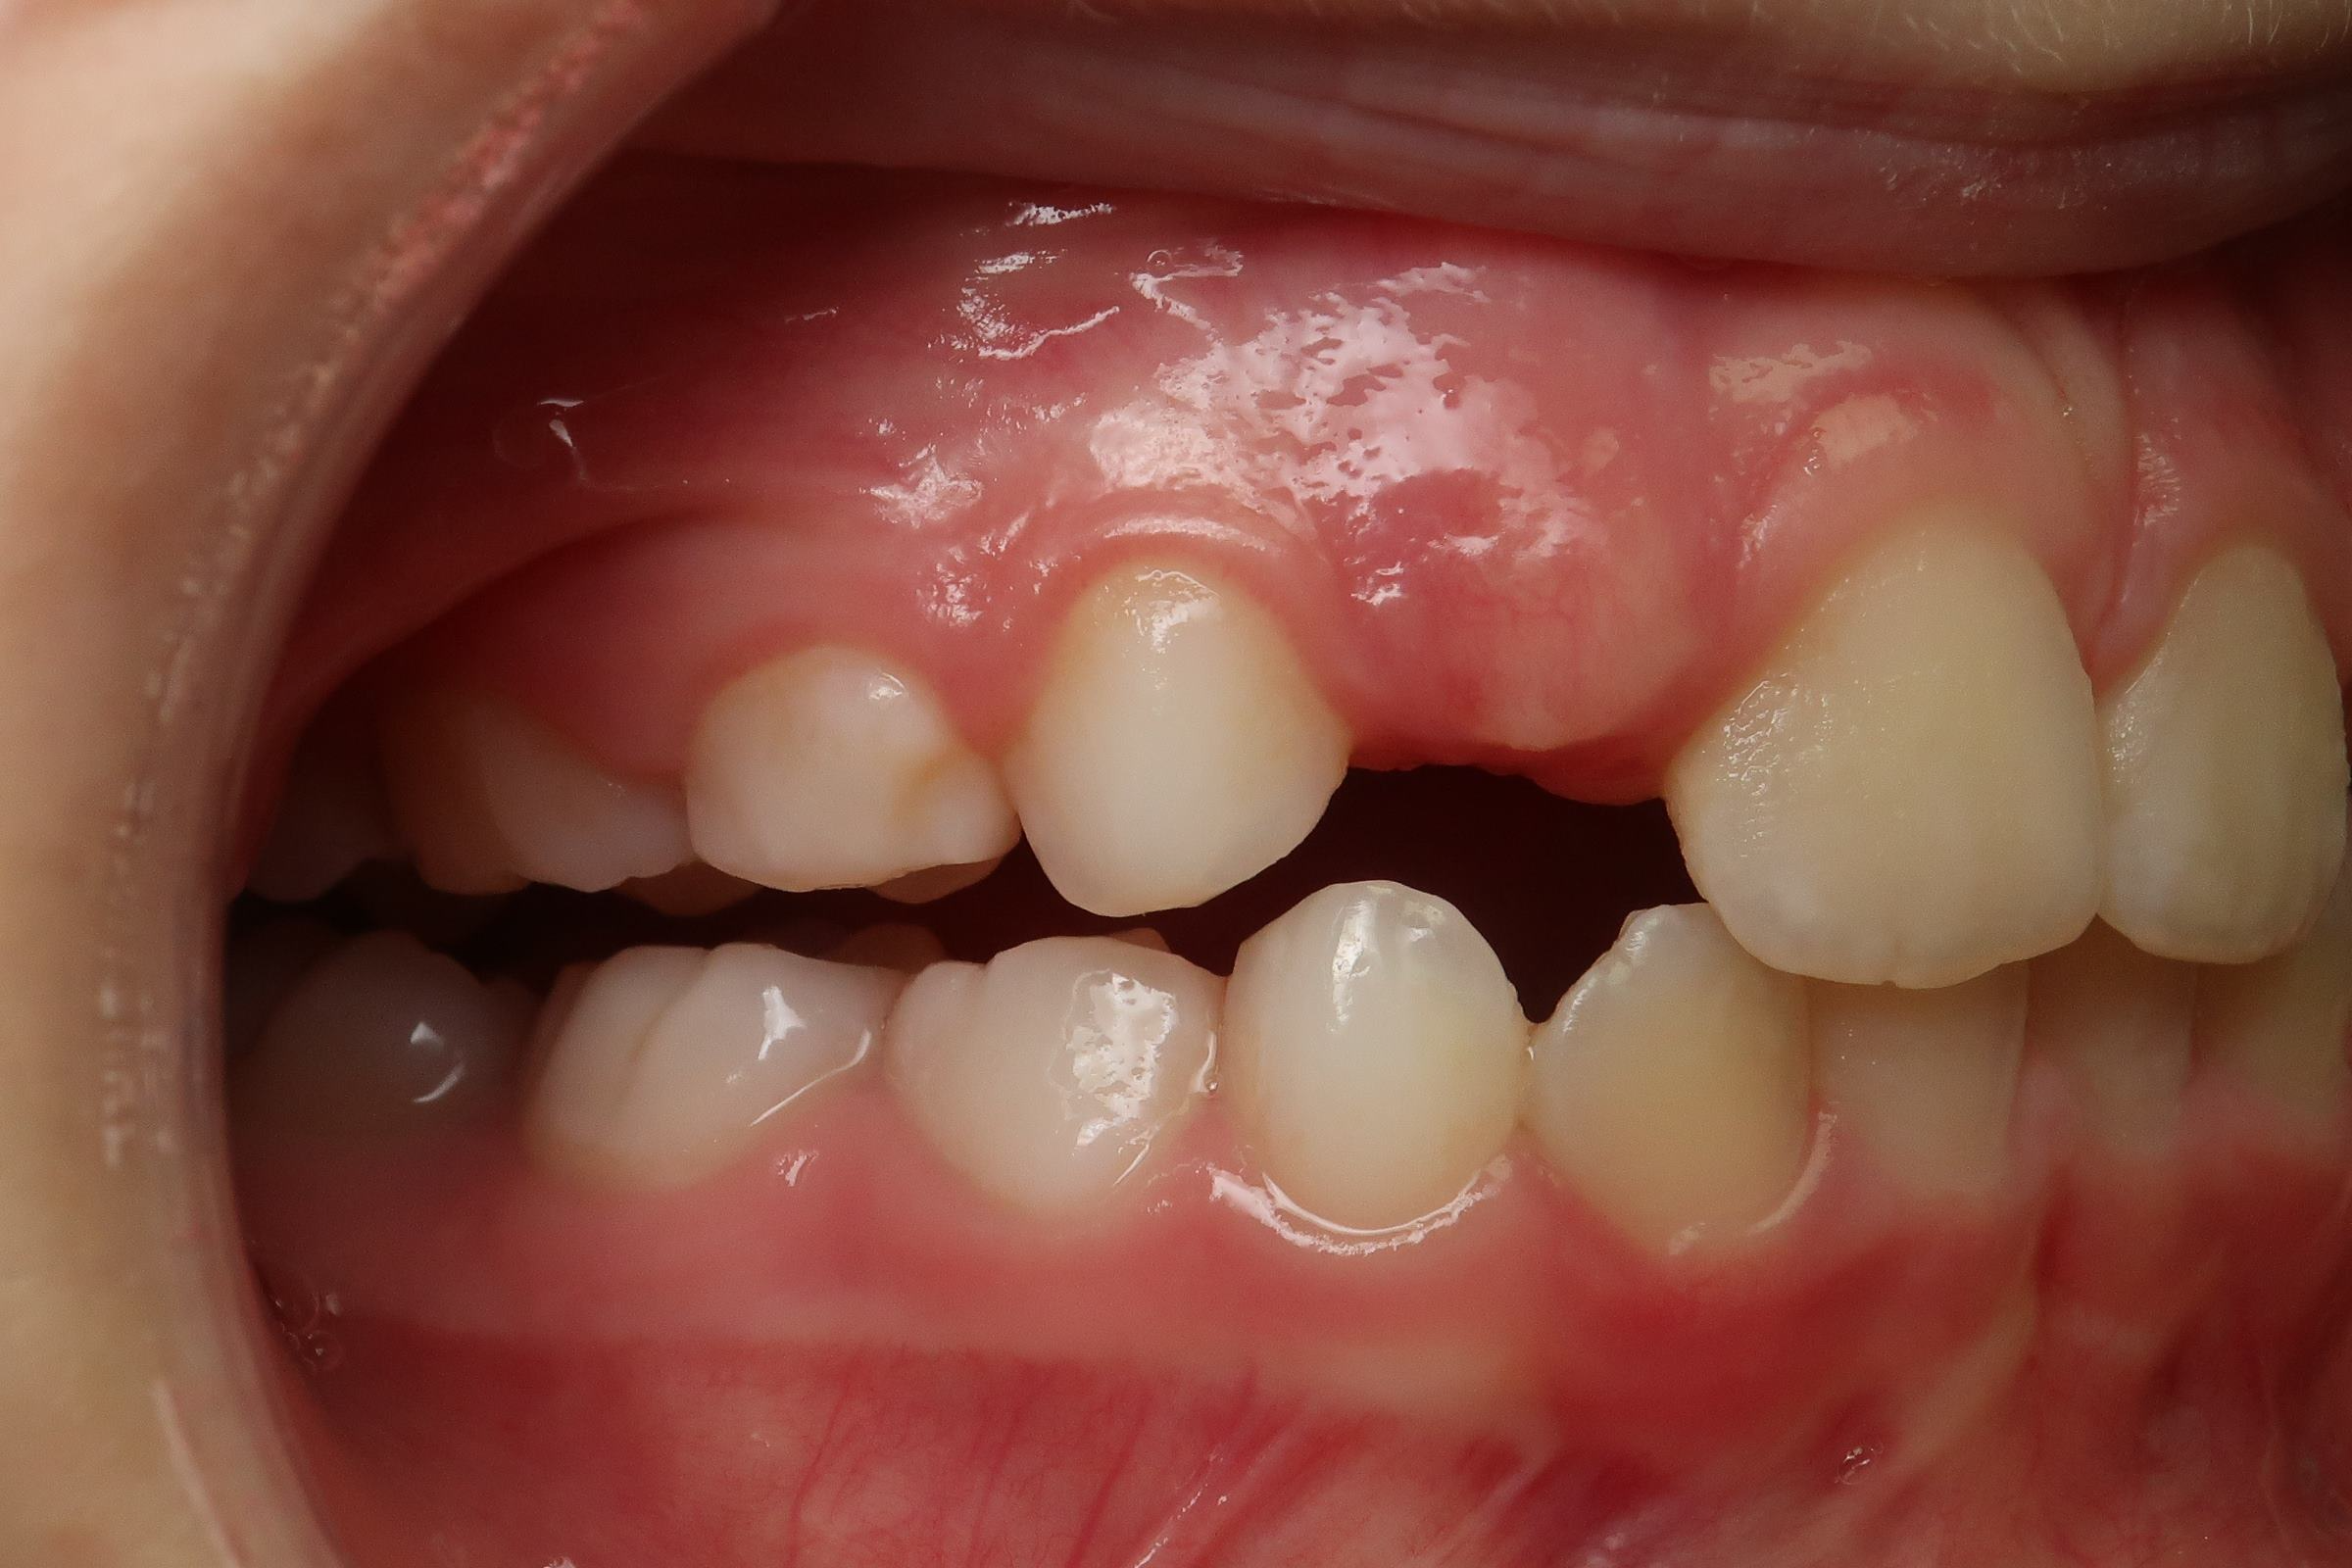

surveillance de la dentition pendant 16 mois

sectionnel multibagues pendant 24 mois

bilan début et en cours de traitement